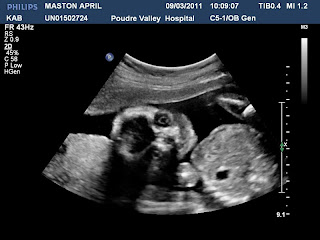

Brad, Cadence and I went to see pictures of the baby, yesterday, at our 20 week ultrasound. Cadence was very interested and asked a lot of questions. She said that the baby looked squished and said that I need to make my tummy bigger to give it more room. I told her I'd work on it.

Isn't he/she cute? Of course! Just like every other ultrasound picture of a baby.:) Our ultrasound tech said that that is good, though. This is the only time in life when you want your baby to look like everyone else. It's when the baby doesn't look like all the other pictures that they worry. So, woo-hoo for uniformity!

It's laying on his/her tummy in this picture (head to the right, feet to the left). He/she is around 11 ounces and roughly the size of a banana, now.